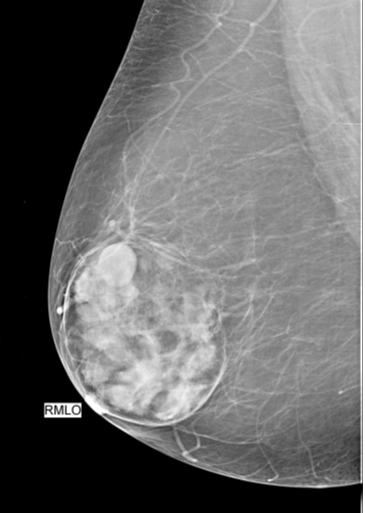

Breast Hamartoma.

“Breast within a breast”, or “sausage appearance”

association: cowden syndrome